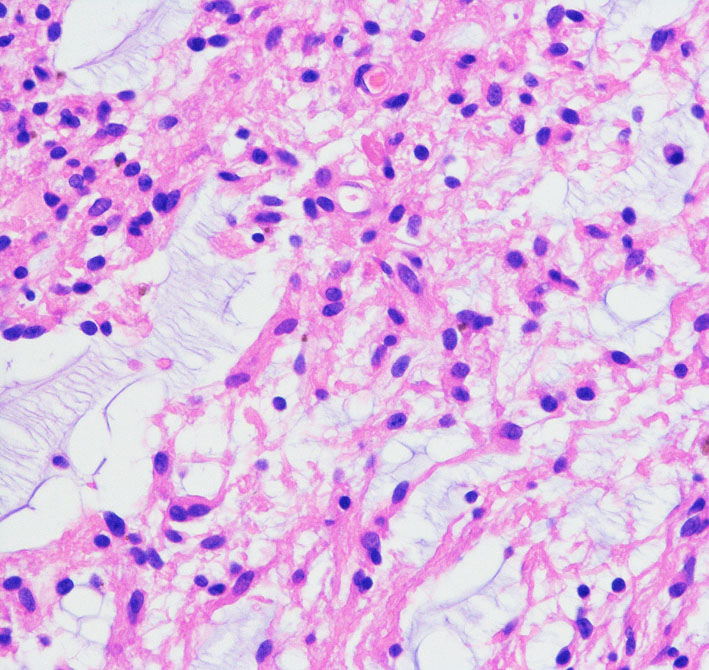

病理所見では,幼児型のpilomyxoid astrocytomaの部分が混在します。その部分が増殖と腫瘍増大に関わっています。T2強調画像で高信号でガドリニウム増強される部分です。

myxoidな部分です。右下のMIB-1染色では3%ほどの陽性率であり,数年単位では腫瘍増大があり得ることを示します。柔らかく出血性で吸引摘出できる部分の腫瘍です。IDH wild type, BRAFV600 wild type, H3K27 wild type, FGFR1 N546K mutationでした。